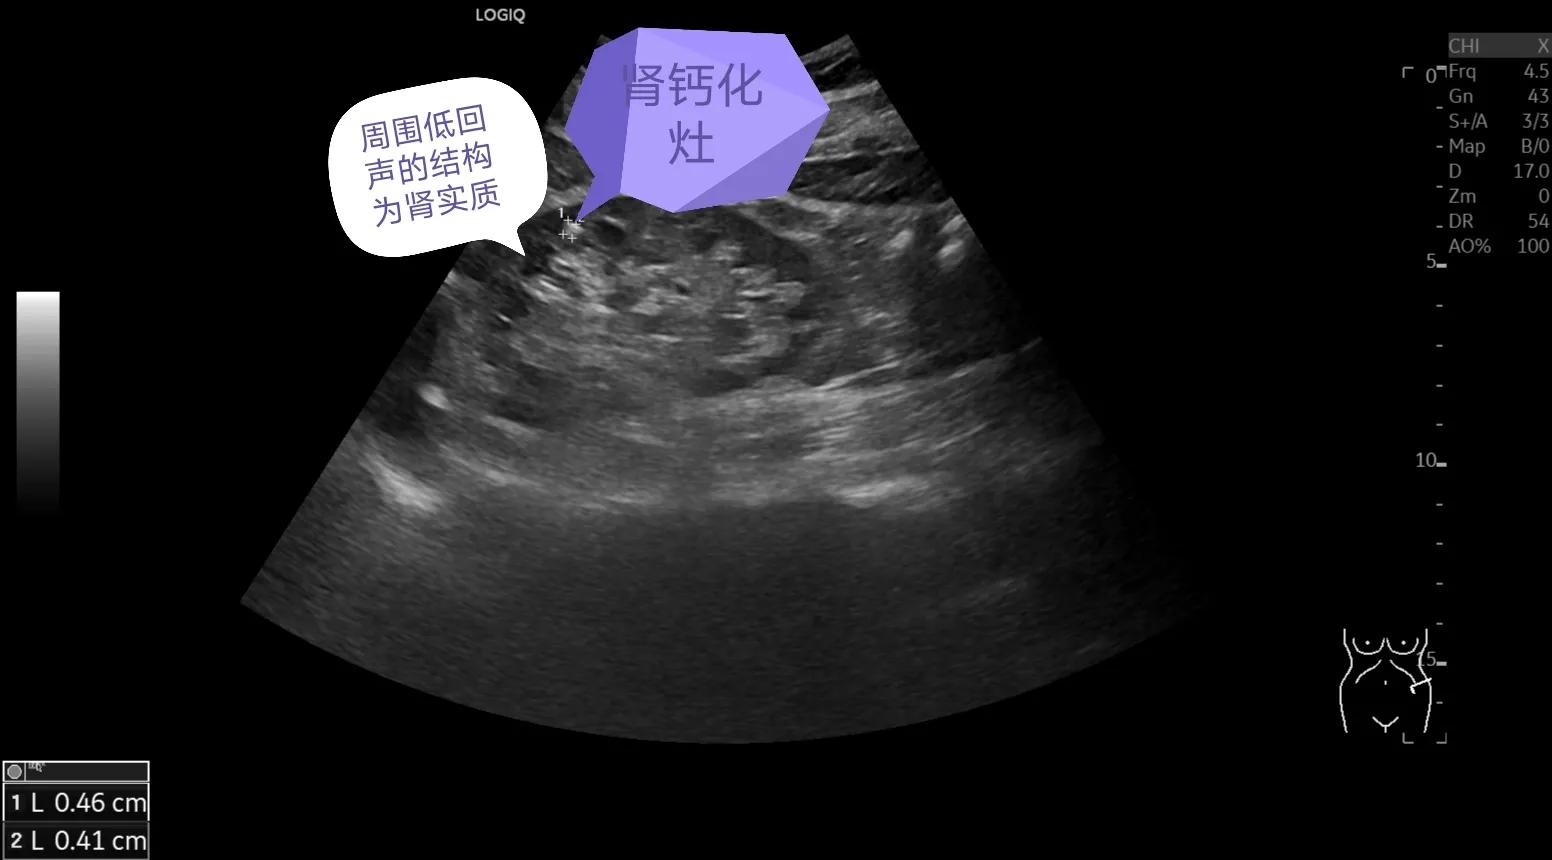

图中这个亮亮的强回声斑就是钙化灶,大小8.8*6.4mm

肾钙化灶同样表现为肾内的强回声斑,看到这大家可能疑惑了,“大夫,刚刚区分了肾结石和肾结晶,这个明白了,一个大一个小,这会肾钙化灶也是强回声斑,这个怎么区别,这不又混在一起了”,大家别着急,图像上他们确实类似,但是发生的位置上他们是有严格的区别的,我们上面说了结晶是尿中析出的结晶,尿液在肾脏形成后通过肾乳头开口流入肾小盏—肾大盏—肾盂—输尿管—膀胱—尿道—排出体外,而肾小盏、肾大盏、肾盂和输尿管结构再加上内部的血管、脂肪结构统一构成了肾脏集合系统,又称为肾窦,这个结构在咱们超声上表现为高回声,而周围的低回声为肾实质结构,这个肾脏的回声之前的内容咱们讲过,大家可以找出来看一看,说了这个知识大家就明白了吧,肾结石和结晶一定是发生在肾脏的集合系统内,而肾钙化灶则发生在肾实质内,这是他们的本质区别,下面再给大家分享几张图,直观的感受一下。